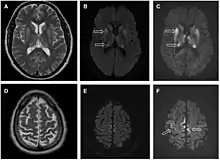

MR af cerebrum hos patient med iCJD. Hyperintensitet i nuclei caudati og putamina på bl.a. T2-vægtet sekvens (A) samt i cortex på diffusionsvægtet sekvens (E og F).

MR-scanning af hjernen kan anvendes til non-invasiv diagnostik. Stærkt signal på T2-sekvenser i nuclei pulvinares indikerer vCJD (høj sensitivitet og specificitet). Radiologiske tegn på sCJD er bl.a. stærkt signal på diffusionsvægtet MR i nucleus caudatus og putamen og evt. cortex cerebri, men disse har dog lavere sensitivitet end tegnene for vCJD.[4]